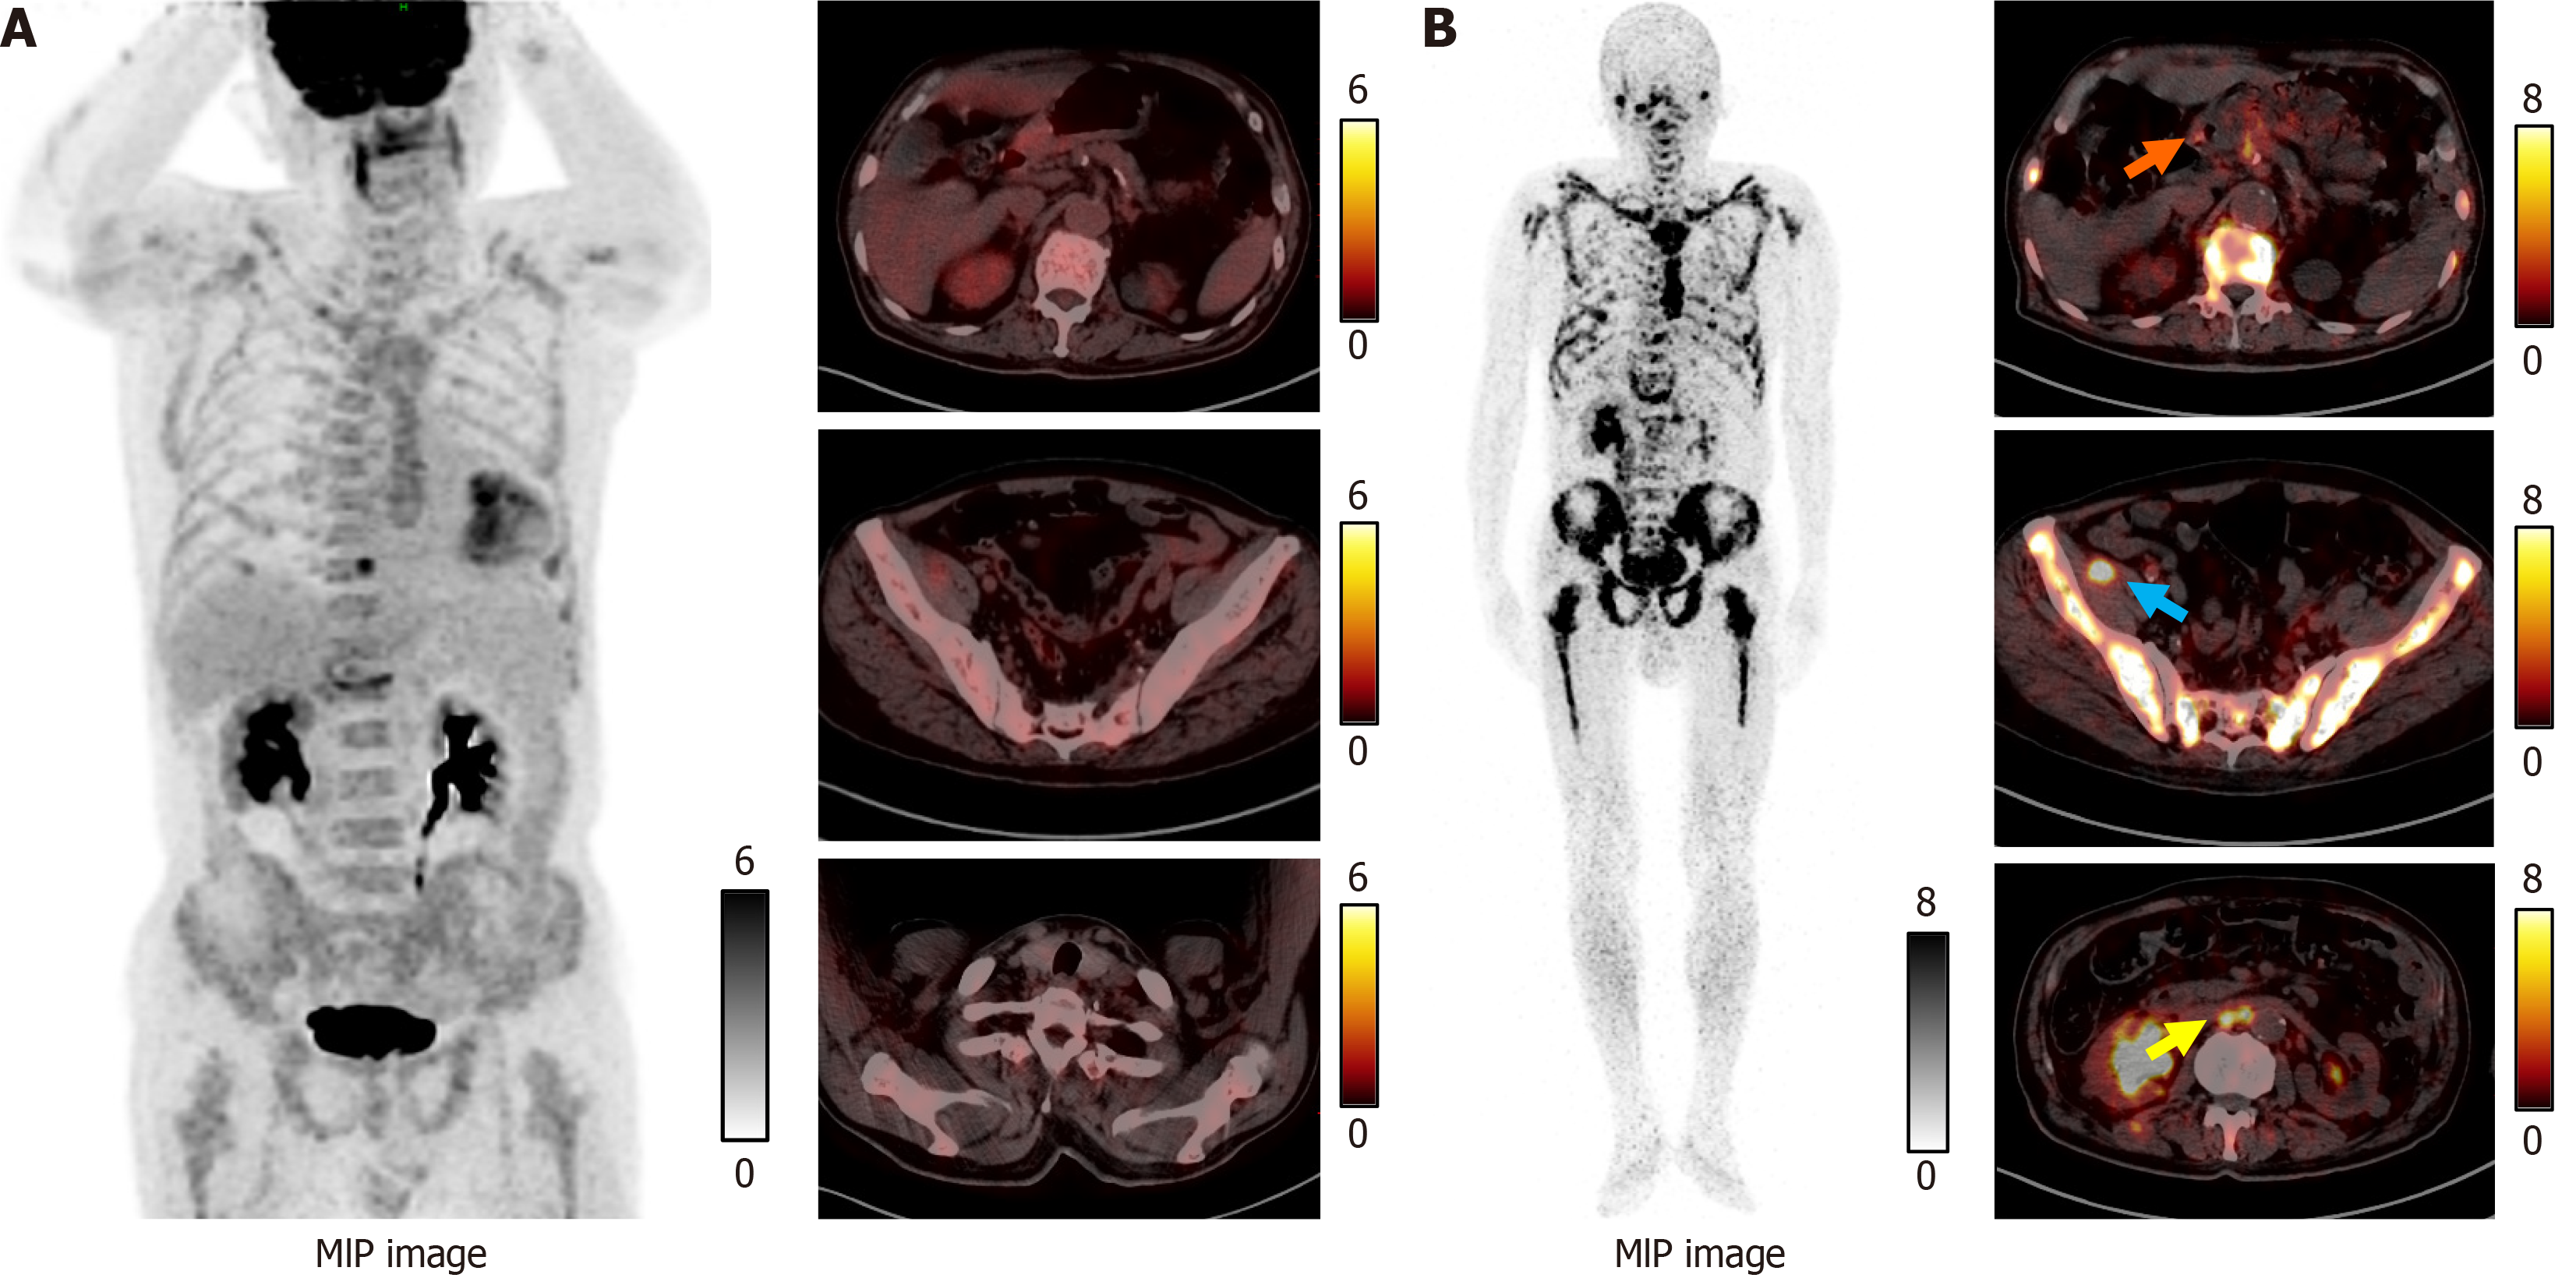

Figure 3 Fluorine-18 fluorodeoxyglucose and gallium-68-labeled fibroblast-activation protein inhibitor positron emission tomography/computed tomography images.

A: No obvious fluorine-18 fluorodeoxyglucose uptake was seen in the gastric antrum, pelvic cavity, or parathyroid region; B: Axial-fused gallium-68-labeled fibroblast-activation protein inhibitor positron emission tomography/computed tomography revealed increased uptake in the gastric antrum [maximum standardized uptake value (SUVmax): 5.52], right pelvic (SUVmax: 15.10), and abdominopelvic metastatic lesion (SUVmax: 10.50) (arrowhead). MIP: Maximum intensity projection.